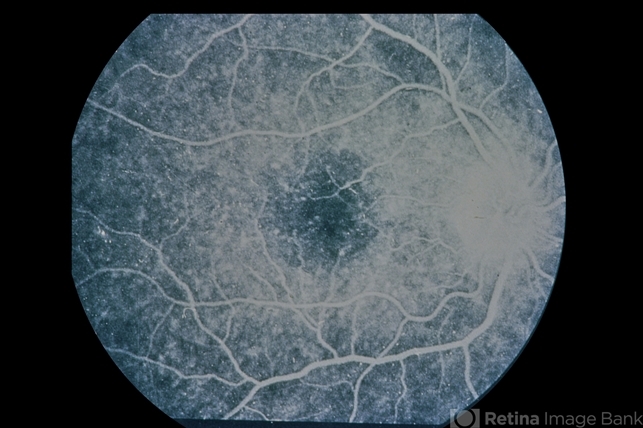

- Ring 17 Chromosome

- Condition/keywords

- crystalline retinopathy

- 3-year-old patient, crystalline retinopathy; 20/30 roughly; epilepsy.